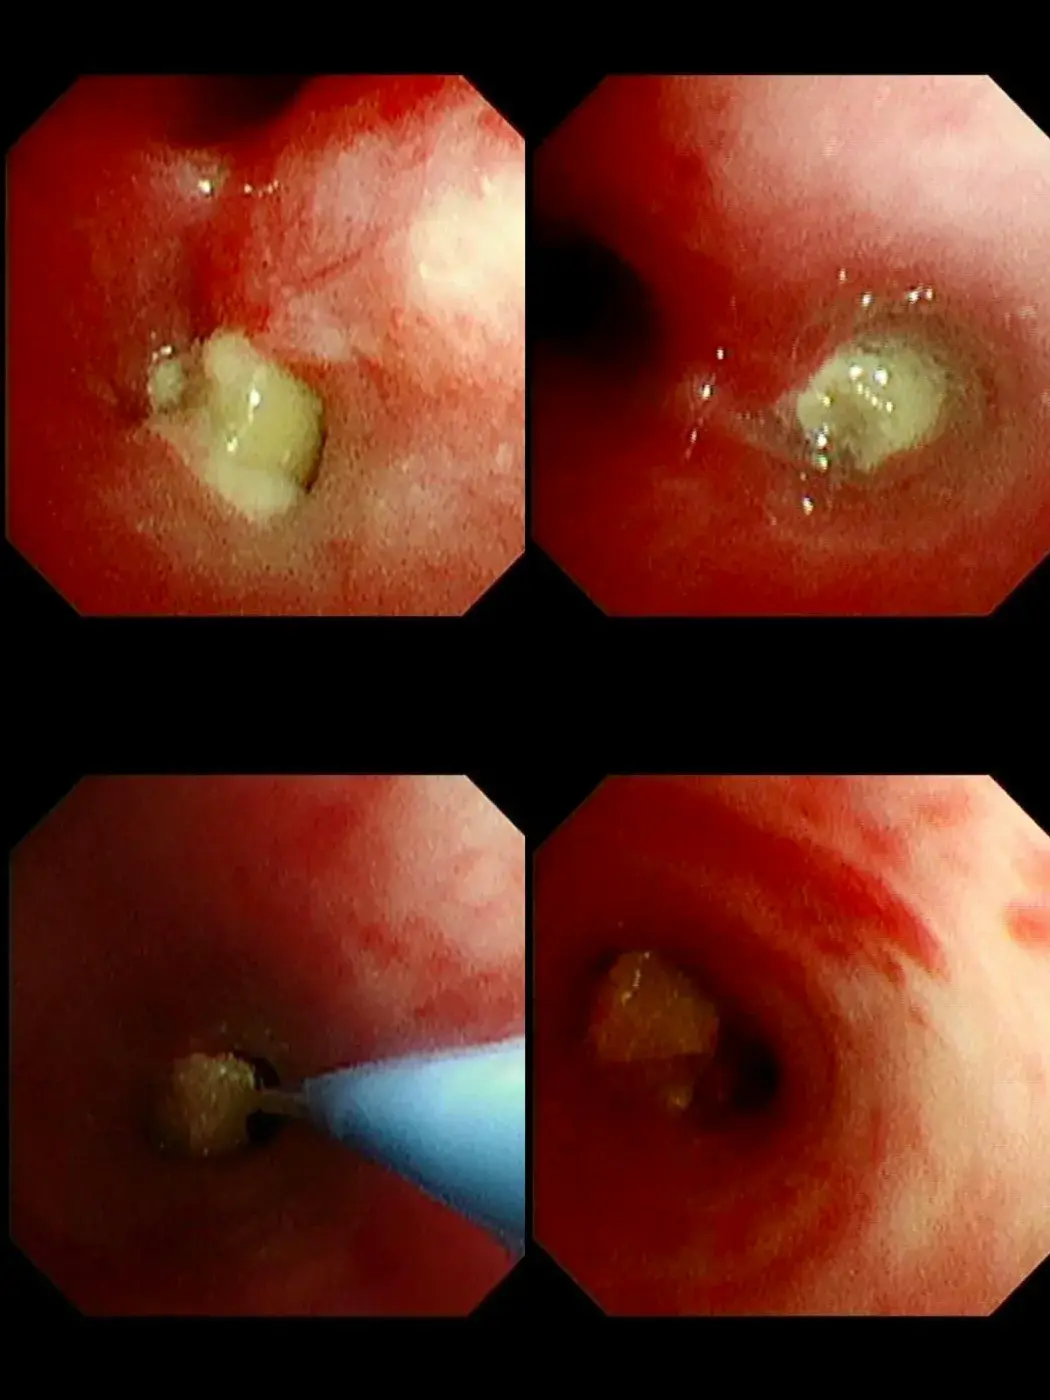

เหตุการณ์นี้เกิดขึ้นเมื่อคุณย่าป้อน ถั่วลิสงแบบเต็มเมล็ด ให้หลานวัย 1 ขวบทาน หลังจากนั้นเพียง 3-4 วัน เด็กเริ่มมีอาการผิดปกติ คือ ไอเรื้อรังและมีเสียงหายใจหวีด เมื่อนำตัวส่งโรงพยาบาล ผลเอกซเรย์พบว่าถั่วลิสงหลุดเข้าไปอุดกั้นในหลอดลม จนทำให้ลมไม่สามารถเข้าสู่ปอดได้ ส่งผลให้ปอดบางส่วนยุบตัวลง

ความยากในการรักษา: เนื่องจากสิ่งแปลกปลอมติดค้างอยู่นานหลายวัน ร่างกายจึงสร้างเนื้อเยื่ออักเสบขึ้นมาหุ้มถั่วไว้ ทำให้ถั่วมีลักษณะลื่นและขยับไปมาในหลอดลม (Dancing Peanut) ทีมแพทย์ต้องใช้ความชำนาญอย่างสูงในการส่องกล้องคีบออกมาเพื่อช่วยชีวิตเด็ก